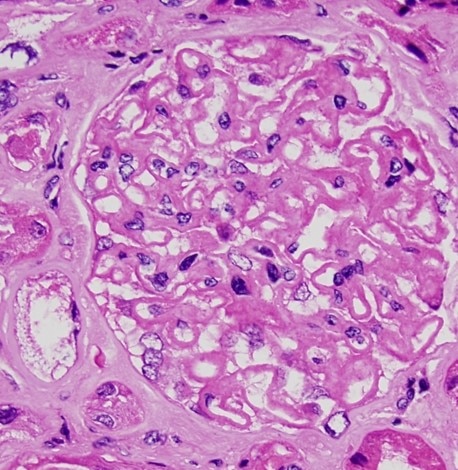

The Clinical Nephrology Section studies various kidney diseases, including membranous nephropathy and focal segmental glomerulosclerosis. The goal of our research is to better understand the evolution and outcomes of these kidney diseases and find treatments that may be more effective and less toxic.

Research Images